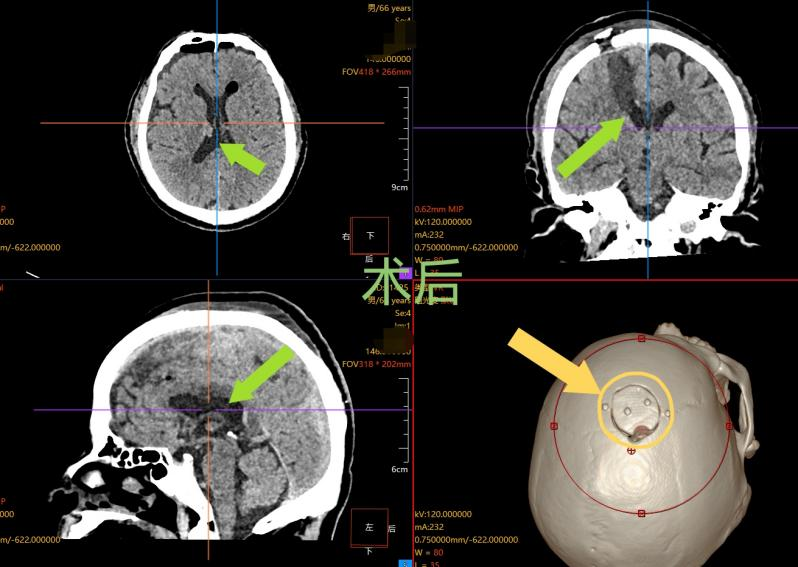

整场手术过程顺利,术后复查 CT 显示,张先生颅内的血肿已被满意清除,受压的脑组织得到有效减压。更令人振奋的是,这场高难度手术仅在患者头部留下长约 4 厘米的微小切口,骨瓣不足 3 厘米 —— 相比传统开颅手术的切口,创伤被降至最低。

得益于微创手术巨大优势,张先生术后恢复速度远超预期:头痛、呕吐等症状很快消失,神志转清,神经功能也得到最大程度保留。目前,张先生已能自主步行出院,家属对治疗效果给予高度认可。